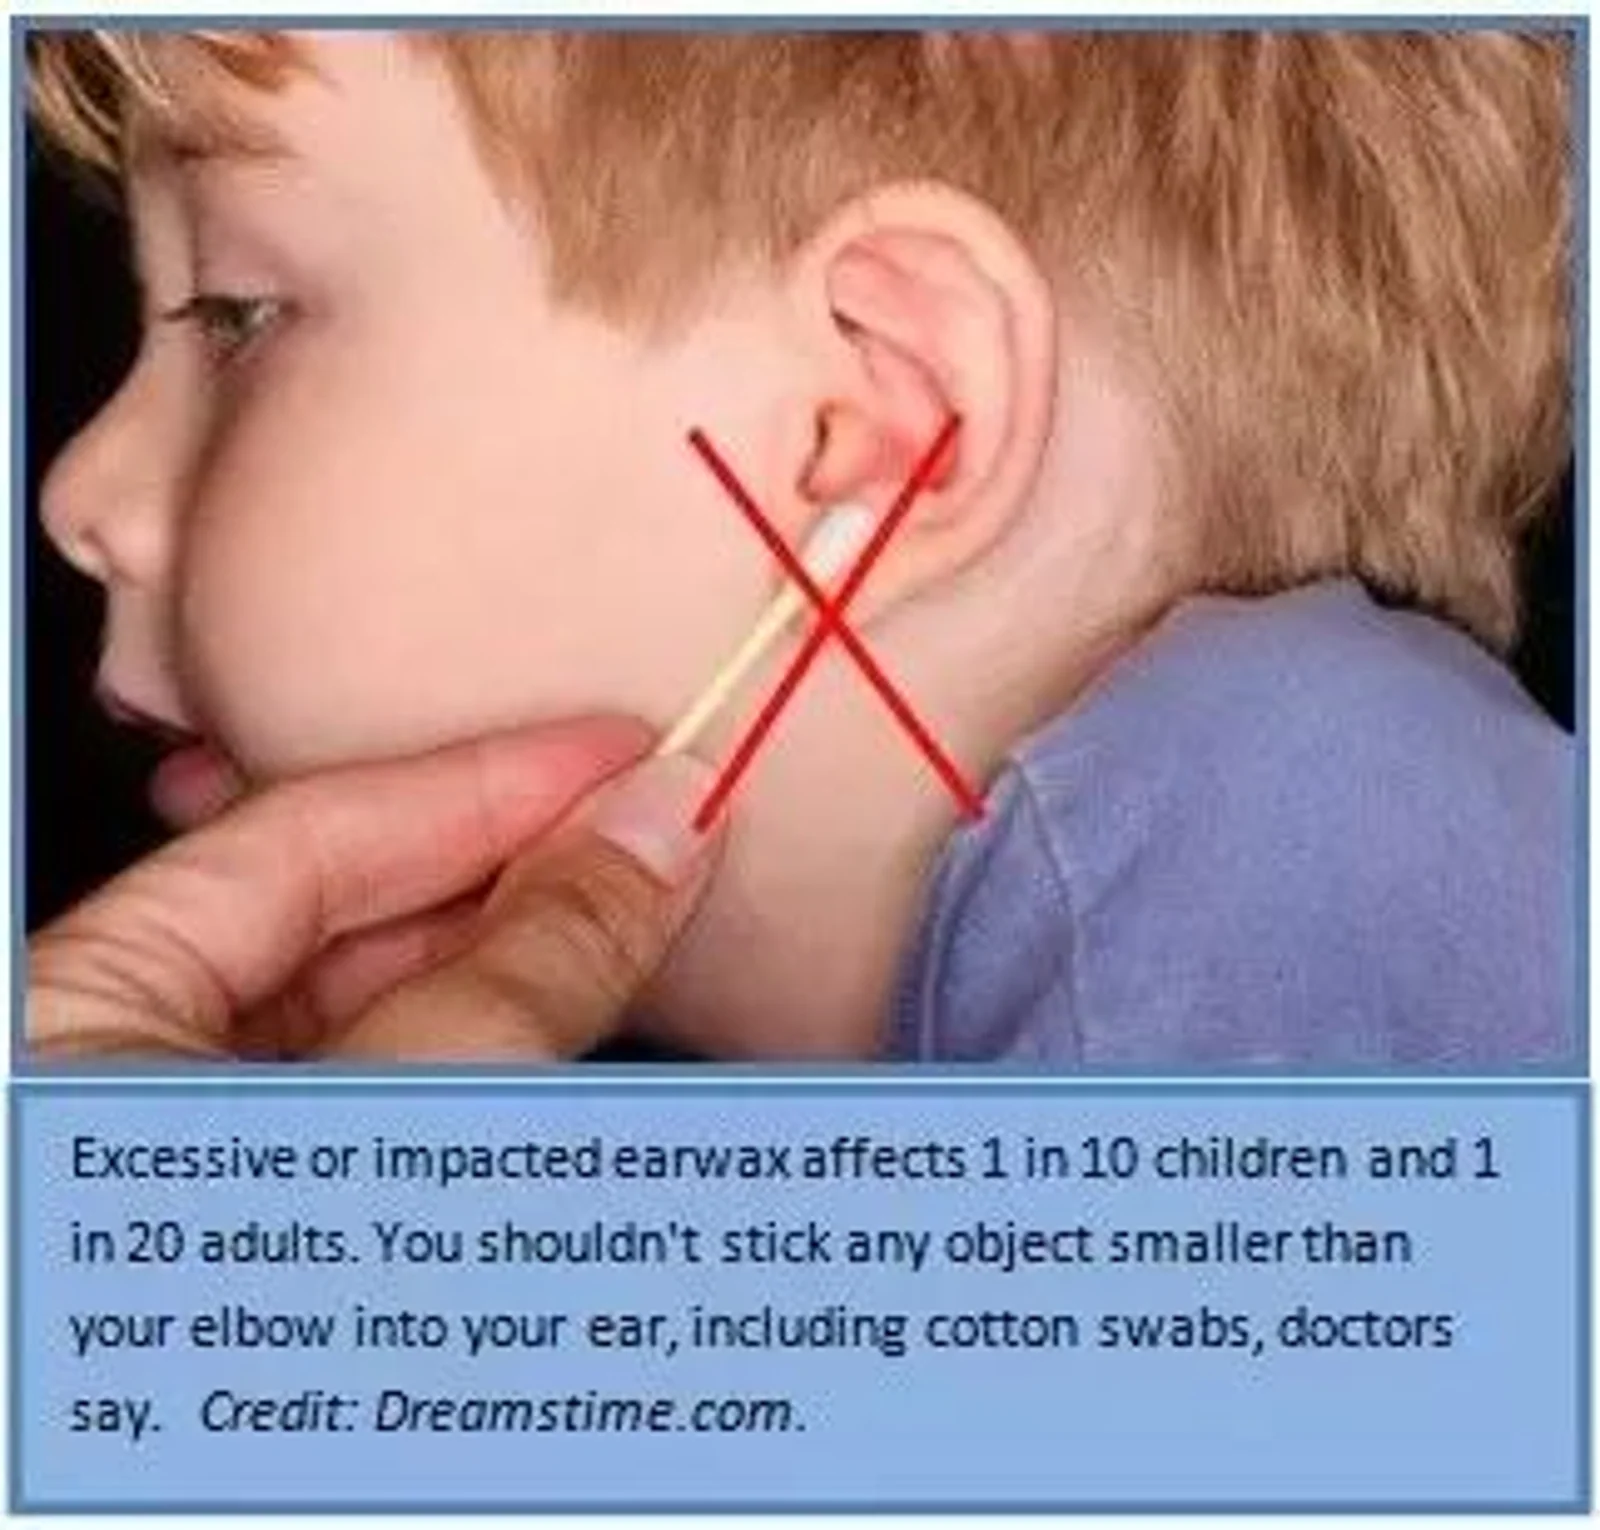

但是这种小动作会造成大毛病,尤其是喜欢用棉签的掏耳朵的小伙伴,赶紧收手!不少人因此被送进医院。

长期棉签掏耳朵恐被送进医院 上世纪20年代,棉签的问世,其一大用处就是用来清洁婴儿的耳朵,然而却因为棉签造成了很多人耳朵受伤,从轻伤到重伤都不少见。 据CNN报道,美国每天大约有34多名每年有12,500名 在就诊的儿童中,40%因为觉得耳朵里面有异物,35%因为耳朵出血,17%耳朵痛。经医生诊断,25%的儿童骨膜破裂软组织受伤清洁耳朵惹的祸 医生提醒:千万不要用棉签掏耳朵 其实我们常说的耳屎,就是耳垢,它并不是脏东西,只是耳朵分泌的物质抗菌保护耳道的功能 就算因为耳垢堆积过多,也绝对不能用棉签清理,我们想象中棉签会比一些坚硬物体要柔软,不会对耳朵造成伤害,其实大错特错!用棉签清理耳朵,不但清理不干净,还会适得其反! (美国耳喉鼻科协会特别提醒:千万不能用棉签掏耳朵) 耳垢一般只出现在外耳道,但是如果用棉签掏耳朵,会将耳垢推向耳朵更深处,造成耳垢难以排出,在医学生称为耵聍栓塞 如果洗头洗澡时,耳朵不小心进水了,阻塞在耳朵里的耳垢会吸水膨胀,酸性的耳垢会腐蚀耳道深处的皮肤,不仅会造成耳朵疼痛引起感染 经常掏耳朵还会造成恶性循环。导致耳垢分泌异常有利于细菌生长流黄水,听力下降 正确清理耳朵的方式 其实健康的外耳道是有自洁功能 当然,外耳道的自洁功能并没有那么强大,总会有顽固的耳垢不能被排出,这也就是为什么我们总是会觉得耳朵里面有耳垢。 那么能不用棉签,该怎么清理呢 1、在沐浴时,用少量的温水清洗耳朵,马上用消毒过的棉签擦干耳道。 2、可以用盐水清理耳朵。轻轻将盐水滴入耳道中,头摇晃几下,然后冲洗干净。 2、利用婴儿油、矿物油等专门清洁耳道的清洁油来清理。清理前,最好将油涂抹在手上测试,确定不会有过敏反应。 3、可以用氧化氢这种专门清洁耳道的液体来清洁耳朵。 4、如果耳朵出现疼痛出血耳鸣等问题,不要轻举妄动,及时就医。 所以小伙伴们如果觉得耳朵不舒服,不要图一时爽快,拿起棉签就开始掏,还是要寻求科学的方法